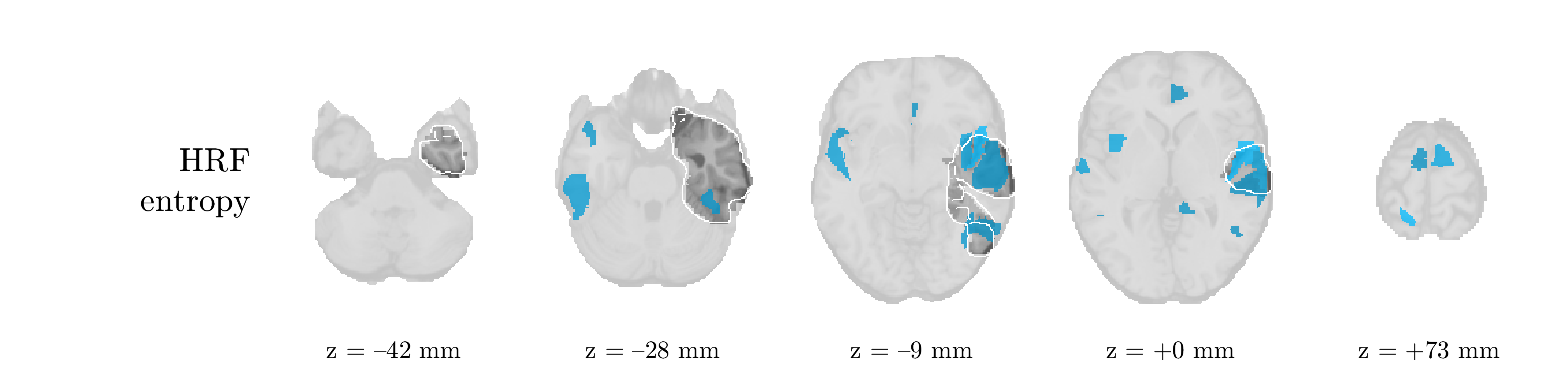

We analyze the solution with sources. Figure 1 shows the EEG signatures and HRF waveforms. One of the sources is highly correlated to the MWF reference (in grey), which was already known from Table B.3. This IED-related source had a typical low-frequency spectrum, which is expected for the typical spike-and-wave interictal discharges. The topography is relatively diffuse, although the highest amplitudes are mostly in the left hemisphere. This is in accordance with the lateralization of ictal onset zone (left temporal lobe, cfr. Table 1). There are some noteworthy observations to be made about some of the other components. The fourth has an unusually sharp spectrum, is mainly localized on two nonadjacent center electrodes, and is sustained for a single period of many seconds Hence, this component likely captured an artifact (of yet unknown origin), although we spotted no large-amplitude changes in the EEG itself. Similarly, the third source is only present at one frontal electrode, and exists in a frequency range above 20 Hz. It might represent a muscle artifact, e.g., due to frowning or twitching of some muscles in the forehead. The HRFs of all ROIs are shown in Figure 1(b). Two of the basis functions seem to have converged to a very similar waveform, which is an unfortunate possibility if two initial HRFs are too close to the same local optimum in their respective parameters. This reduces the expressive power of the basis set, which is clearly visible, since many ROIs have a nearly identical HRF. One of the twenty ROIs with the highest-entropy HRF overlapped the IOZ, although clearly this HRF (bold line) is not among the most dissimilar waveforms for this patient. This is also visible in Figure 2: both the HRF entropy and extremity maps show a small overlap with the delineated IOZ. Despite the good correspondence in the EEG domain, no significant (de)activation of the IED-component is found inside the IOZ.

We analyze the solution with sources, and show the results in Figure 3 and 4. As for patient 1, we found a source which is strongly correlated to the MWF envelope, and which had a mostly low-frequency behavior characteristic for spikes. The topography is mostly uninformative, and does not clearly correspond to the patient’s clinical data. The third source is mostly present at both sides of the head, is very sparsely active in time, and has a high-frequency content: this is most likely an artifact due to the neck muscles. Again, there is one of the highest-entropy HRFs which belongs to a ROI in the IOZ. Now, the waveform is clearly resolved from the other HRFs, through the strong initial dip (before 0 seconds). Such a dip is sometimes observed in HRFs, but its underlying physiological mechanism is not yet fully understood. It is possible that this dip reflects altered vascular autoregulation near the IOZ (cfr. the explanation in the Section 1 of the main text), or a rapid depletion in oxygen due to IED generation (before the IED becomes visible on the EEG). Figure 4 furthermore shows that the IED-related component is significantly active in parts of the IOZ, and deactive in others. As mentioned earlier, this deactivation may or may not be due to errors in sign correction. Interestingly, the ROI with the high alteration in neurovascular coupling is distinct from both the activated and deactivated ROIs.

We analyzed the solution with sources, and show the results in Figure 5 and 6. There is one source which is mostly correlated to the reference (but not extremely, see also Table B.3). This source had a right-temporal focus, conform the diagnosis in Table 1. The second source illustrates the phenomenon of an erroneous sign exchange between the spatial and spectral profiles. Also one of the HRFs has a negative polarity, which is a failure of the sign correction procedure (in this case, because there is exceptionally no positive overshoot). However, the HRF variability metrics are still interpretable, and indeed two ROIs among the ones with the highest-entropy HRFs overlap with the IOZ. The IED component is significantly active in a tiny portion of the IOZ (cfr. Figure 6). The second source is significantly active in symmetrical parts of the parietal lobe. Given its ongoing fluctuation over time, we hypothesize that this source captures a resting state network (RSN).

We analyze the solution with sources, and show the results in Figure 7 and 8. There is a clear IED-related component, with a very high correlation to the MWF reference, a typical spectrum, and an anterior-temporal focus, which corresponds very well to the patient’s diagnosis (cfr. Table 1). The fifth source seems present at only one channel, and has spectral harmonic at Hz and Hz. One of these peaks is reminiscent of the fourth component in patient 1. As Figure 8 shows, the HRF entropy and extremity prove to be strong biomarkers for the IOZ in this case, and also the significant IED activation and deactivation allow correct localization. In Figure 7, it is clear that some HRFs may still have the wrong sign, which means that the interpretation of ‘active’ and ‘deactivated’ is flipped in those ROIs. Hence, regions of significant deactivation are in fact significantly activated. The fourth source had a significant overlap with the auditory RSN, and its spectrum reveals activity in the band.

We analyze the solution with sources, and show the results in Figure 9 and 10. One source is strongly correlated to the MWF, while the other source is likely an artifact, given its very sparse temporal profile. Both sources coincide at one high-amplitude peak, by which we infer that this is probably an artifactual period in the signal. Indeed, when inspecting the original EEG signals, we found high-frequency muscle artifacts at these times. This source also had no significant activation in its spatial map, which corroborates its non-neuronal origin. The IED-related source had a broader spectrum than most other cases, and an uninformative topography. None of the ROIs with high-entropy HRFs is located in the IOZ. The pseudo t-map provides correct localization of the IOZ, however.

We analyze the solution with sources, and show the results in Figure 11 and 12. We found a clear IED-related component, with a characteristic spectrum and a topography which is backed up by the patient’s diagnosis (left anterior-temporal IOZ). The fourth source has a very similar topography and spectrum to the fifth source in patient 5. One HRF inside the IOZ had a high-entropy, and is distinguishable from the others by its very sluggish waveform, i.e., it is smeared out in time, with no sharp over- or undershoot. Also the pseudo t-map provided an accurate localization of the IOZ. Notably, in this patient, the extremity metric misses the deviating HRF in the IOZ (while the entropy metric picks it up). The second source overlapped with the frontal part of the default mode network (DMN), and is active in the and low bands.

We analyze the solution with sources, and show the results in Figure 13 and 14. We found two components which had correlated time courses. At the time of the peaks, we found higher-amplitude events in the EEG with dubious origin, hence they may or may not be artifacts. One of both components is more strongly correlated to the MWF, and its activation is concordant with the IOZ. The second component shows high overlap with the sensorimotor network. For this patient, none of the IOZ’s ROIs had extreme values of either HRF metric.

We analyze the solution with sources, and show the results in Figure 15 and 16. In this patient, there is only a moderate correlation of a component with the MWF reference time course. This component’s topography (left occipital) agrees with the clinical description, however. The HRF extremity (and not the entropy) is high in a small part of the IOZ. Both the significant IED activation and deactivation allow correct localization as well. The second source seemingly captured high-frequency oscillatory activity in the sensorimotor network, similar to the previous patient.

We analyze the solution with sources, and show the results in Figure 17 and 18. The IED-related source had a high correlation with the MWF reference, but an odd bimodal spectrum. Its EEG topography is very consistent with the clinical description. Both HRF extremity and entropy are useful biomarkers for the IOZ. The IED activation and deactivation maps each had a very small overlap with the IOZ. The second source is temporally sparse and captures high-frequency EEG variations, which we identified as muscle artifacts.

We analyze the solution with sources, and show the results in Figure 19 and 20. Again we observe an IED-related source and a seemingly artifactual source with a spectral peak near 34 Hz. Many of the high-entropy HRFs are highly noncausal, and are associated to ROIs inside the IOZ. Hence, with both HRF metrics, the highest-scoring ROIs provides good localization of the HRF. While there are no significantly active ROIs in the IOZ, there are several significantly deactivated ROIs, which may indicate that the sign standardization was not done flawlessly (cfr. also some of the negative-peaking HRFs for patient 10). Surprisingly, the second source had one significantly active ROI, which overlaps with the IOZ, but which did not match its EEG topography. Hence, the nature of this source remains ambiguous.